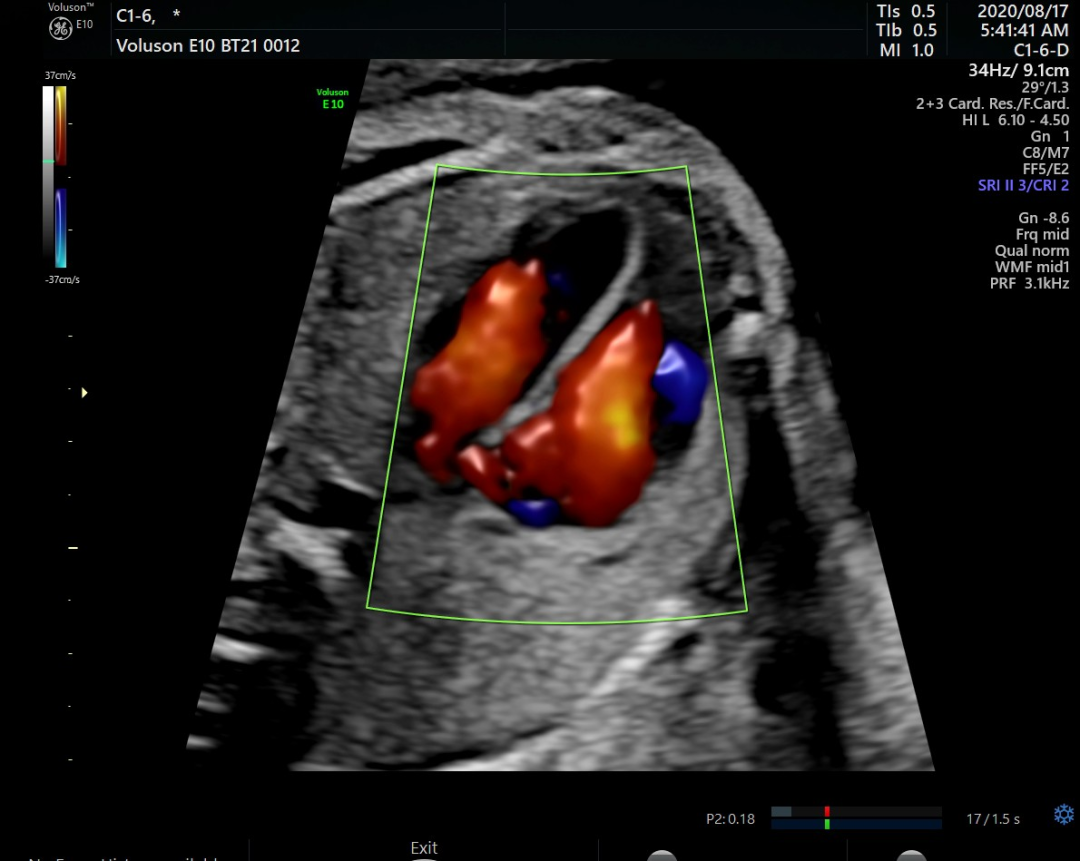

三、胎儿心脏评估

超声设备是进行胎儿心脏检查的首要方法。18-24周胎儿心脏只有普通人指甲般大小,因此胎心检查对于超声图像质量及辅助的诊断工具要求非常高。

Voluson系列超声具备一整套领先的胎心成像技术,支持从胎儿心脏结构到心功能的全面分析,是胎儿心脏检测评估领域的技术领导者。Voluson E10提供优异的图像分辨率,能更快地展现胎心结构和功能,双平面成像技术可实时观察胎心结构和血流变化,帮助临床医生及时作出准确诊断。